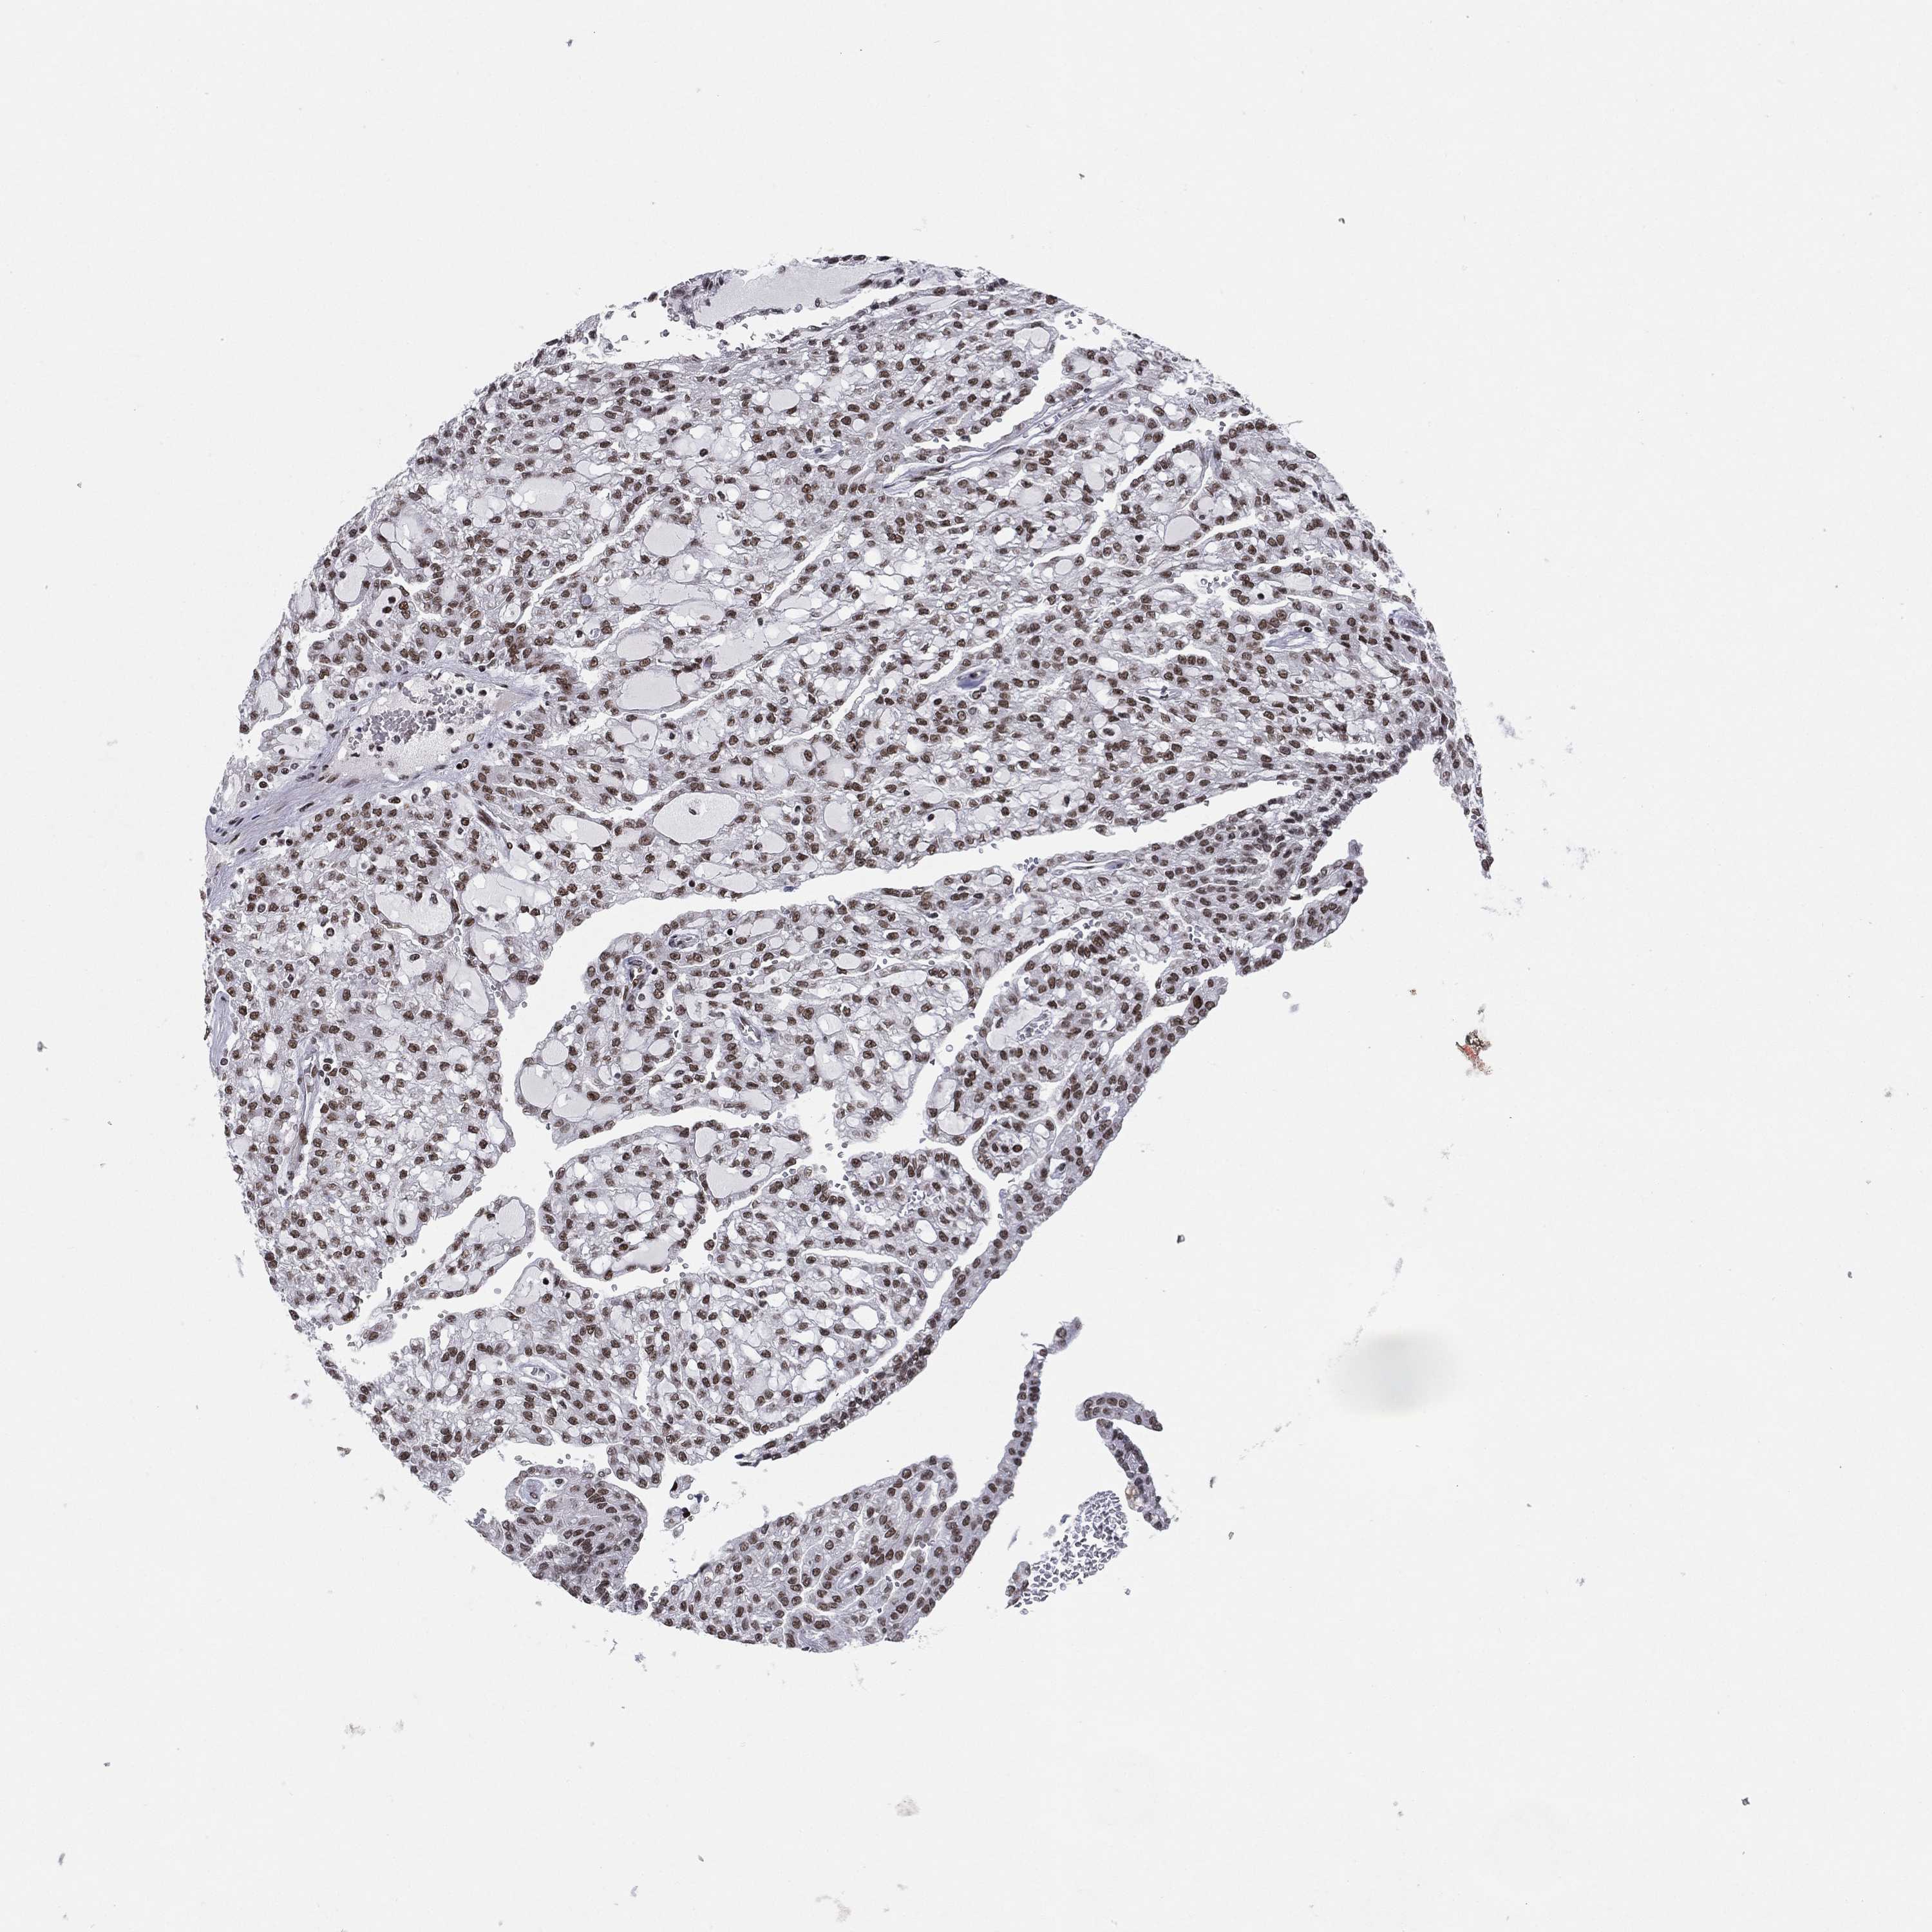

KIDNEY RENAL CLEAR CELL CARCINOMA (TCGA) - Interactive survival scatter ploti

The Survival Scatter plot shows the clinical status (i.e. dead or alive) for all individuals in the patient cohort, based on the same data that underlies the corresponding Kaplan-Meier plots. Patients that are alive at last time for follow-up are shown in blue and patients who have died during the study are shown in red.

The x-axis shows the expression levels (FPKM) of the investigated gene in the tumor tissue at the time of diagnosis. The y-axis shows the follow-up time after diagnosis (years). Both axes are complimented with kernel density curves demonstrating the data density over the axes. The top density plot shows the expression levels (FPKM) distribution among dead (red) and alive patients (blue). The right density plot shows the data density of the survived years of dead patients with high and low expression levels respectively, stratified using the cutoff indicated by the vertical dashed line through the Survival Scatter plot. This cutoff is automatically defined based on the FPKM cutoff that minimizes the p-score. The cutoff can be changed by dragging the vertical line or by entering a cutoff value in the square labeled "Current cut-off".

Under the Survival Scatter plot the p-score landscape (black curve; left axis) is shown together with dead median separation (red curve; right axis). Dead median separation is the difference in median mRNA expression between patients who have died with high and low expression, respectively. It is calculated as follows: median FPKM expression of dead patients with high expression - median FPKM expression of dead patients with low expression. This is intended to aid the user in visually exploring custom cutoffs and the associated p-scores and dead median separation.

Individual patient data is displayed and can be filtered by clicking on one or more of the category buttons on the top of the page. Categories describing expression level and patient information include: high, low, alive, dead, female, male and tumor stages. The scale of the x-axis can be toggled between linear and log-scale by clicking on the "x log" button. Mouse-over function shows TCGA ID, patient information and mRNA expression (FPKM) for each patient.

& Survival analysisi

Kaplan-Meier plots summarize results from analysis of correlation between mRNA expression level and patient survival. Patients were divided based on level of expression into one of the two groups "low" (under cut off) or "high" (over cut off). X-axis shows time for survival (years) and y-axis shows the probability of survival, where 1.0 corresponds to 100 percent.

RTF1 is not prognostic in Kidney Renal Clear Cell Carcinoma (TCGA)

Best expression cut offi

Based on the FPKM value of each gene, patients were classified into two groups and association between prognosis (survival) and gene expression (FPKM) was examined. The best expression cut-off refers the FPKM value that yields maximal difference with regard to survival between the two groups at the lowest log-rank P-value. Best expression cut-off was selected based on survival analysis .

When clicking on this number, the vertical dashed line indicating cut-off, the interactive survival plot, and the Kaplan-Meier curve will be adjusted to show results based on the best expression cut-off.

: 19.06

Median expressioni

Median expression refers to the median FPKM value calculated based on the gene expression (FPKM) data from all patients in this dataset. When clicking on this number, the vertical dashed line indicating cut-off, the interactive survival plot, and the Kaplan-Meier curve will be adjusted to show results based on the median expression.

: N/A

Median follow up timei

Median follow up time refers to the median time (years) after diagnosis with this type of cancer, based on clinical data from all patients in this dataset.

P scorei

Log-rank P value for Kaplan-Meier plot showing results from analysis of correlation between mRNA expression level and patient survival.

N/A

5-year survival highi

5-year survival for patients with higher expression than the expression cutoff.

For melanoma and glioma, 3-year survival is shown.

5-year survival lowi

5-year survival for patients with lower expression than the expression cutoff.

TCGA RNA samplesi

RNA-seq data is reported as average FPKM (number Fragments Per Kilobase of exon per Million reads), generated by the The Cancer Genome Atlas (TCGA) .

Normal distribution across the dataset is visualized with box plots, shown as median and 25th and 75th percentiles. Points are displayed as outliers if they are above or below 1.5 times the interquartile range. FPKM values of the individual samples are presented next to the box plot.

Average pTPM 18.3

Number of samples 521